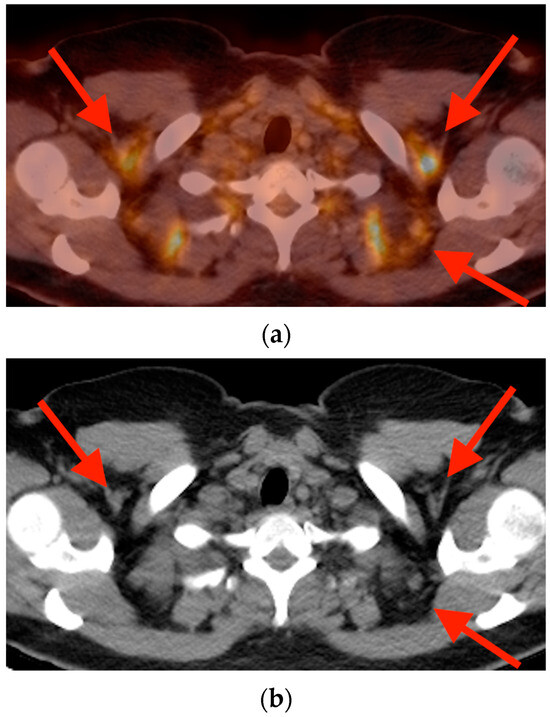

5.2. Brown Fat Activation